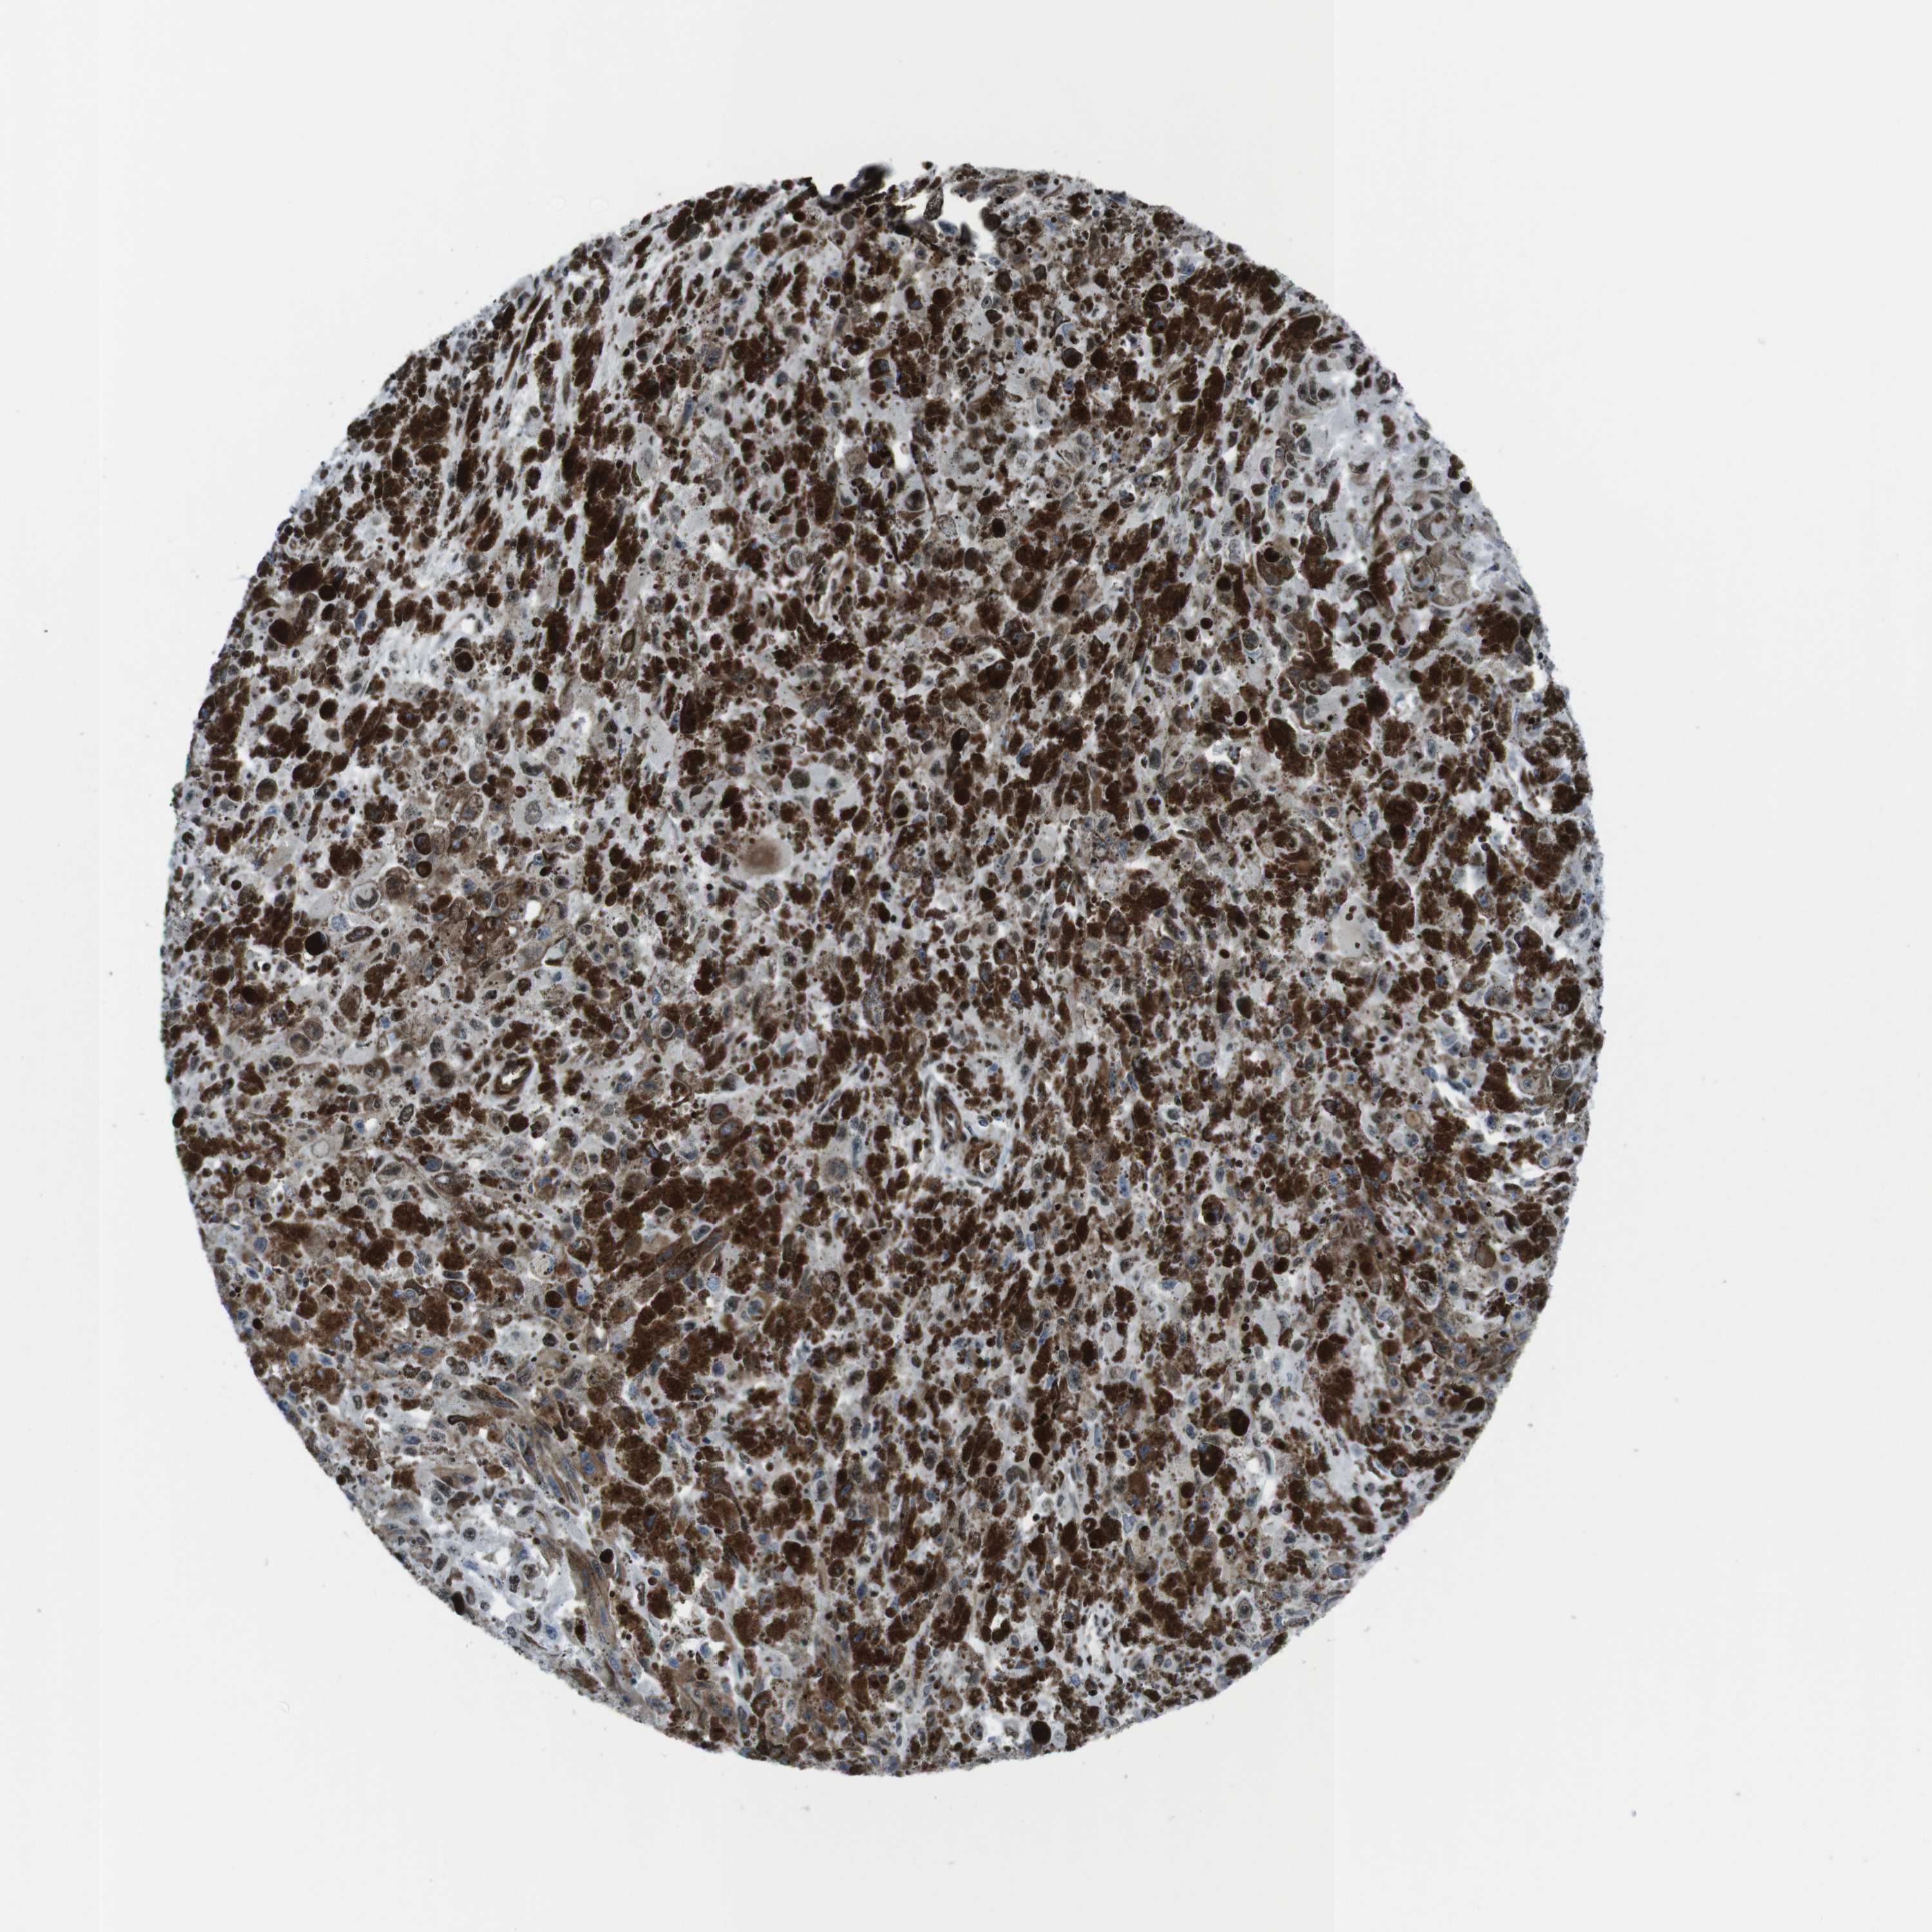

MELANOMA - Protein expressioni

A mouse-over function shows sample information and annotation data. Click on an image to view it in a full screen mode. Samples can be filtered based on level of antibody staining by selecting one or several of the following categories: high, medium, low and not detected. The assay and annotation is described here.

Note that samples used for immunohistochemistry by the Human Protein Atlas do not correspond to samples in the TCGA dataset.

Antibody stainingi

Antibody staining in the annotated cell types in the current human tissue is reported as not detected, low, medium, or high, based on conventional immunohistochemistry profiling in selected tissues. This score is based on the combination of the staining intensity and fraction of stained cells.

Each image is clickable and will lead to virtual microscopy that enables deeper exploration of all samples and also displays staining intensity scores, fraction scores and subcellular localization as well as patient and tissue information for each sample.

Antibody HPA041057

Antibody HPA058707

Antibody CAB011532

Staining

High

Medium

Low

Not detected

Intensity

Strong

Moderate

Weak

Negative

Quantity

>75%

75%-25%

<25%

None

Location

Nuclear

Cytoplasmic/membranous

Cytoplasmic/membranous,nuclear

Malignant melanoma, NOS

Malignant melanoma, Metastatic site